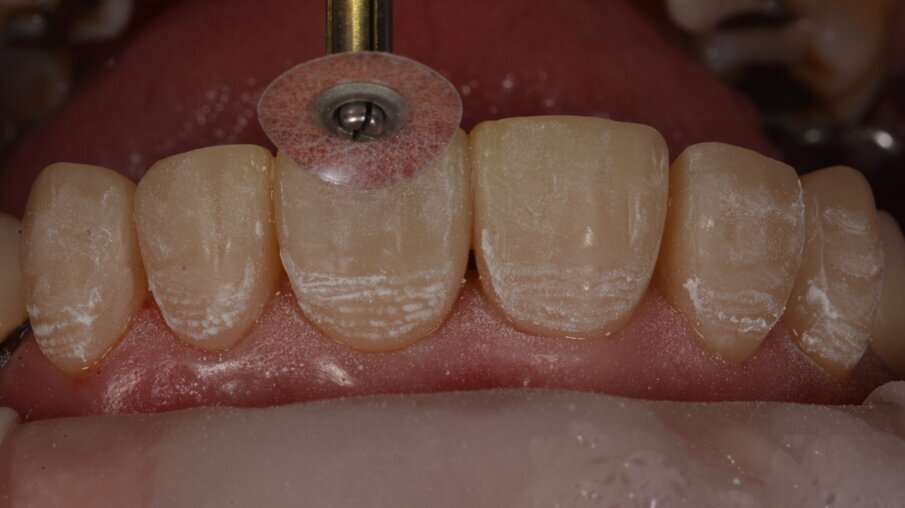

Verdere tertiaire anatomie kan worden aangebracht met een oud rood 3MTM Sof-LexTM Polijstschijfje op laag toerental.

Door zonder waterkoeling te werken zien we duidelijk waar de anatomie is aangebracht.